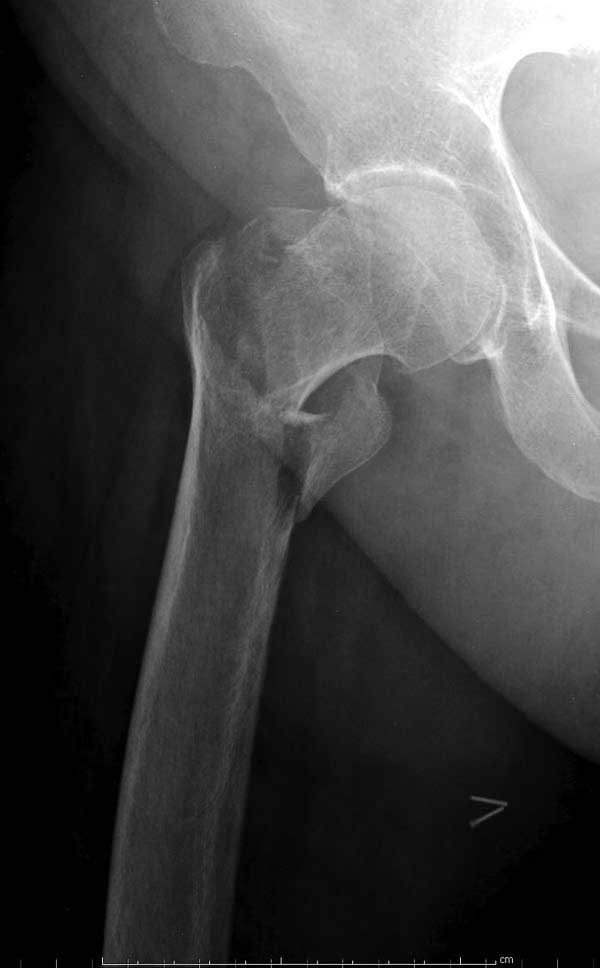

Вторая операция- это фаза сохранения головки бедра. Желательно приложить все усилия и сохранить головку, но, как видно, “фиаско” продолжается. Здесь вместо нейтрализации сил между медиальной и латеральными сторонами была попытка удержать варус. Варус не удержать ни деротационными шурупами о котором говорили и не костными стружками вбитые в шейку, потому что вся нагрузка упирается в головку.

Как отметил Евгений, 95 degree Blade Plate Fixed Angle device  расчитана на восстановление взаимоотношении между головкой и диафизом, а все остальные фиксаторы (Gamma, Afifuxus и др.) работают за счет нагрузки в верхнем полюсе головки. Верхний полюс успели разрушить, и в головке единственное место, который смог бы удержать широкий клинок конструкции, это медиально-низкий сегмент. После установки клинка засчет дистракции можно удлинить конечность на 15мм, а добавленный в дефект ауто-графт закончил бы дело.